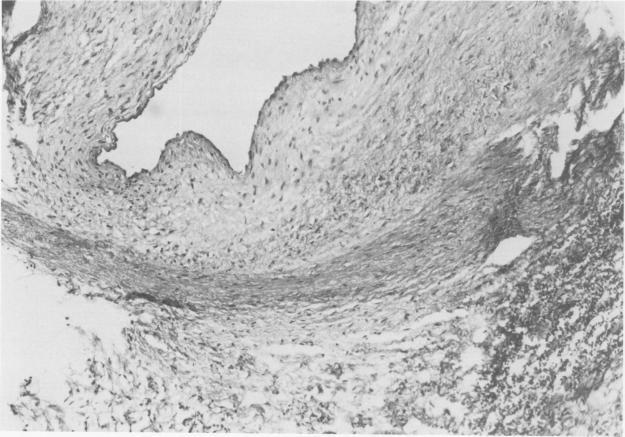

We have used two methods to maintain ductal ppatency in 13 newborns during surgery for congenital cardiac malformations: prostaglandin E1 (PGE1) infusion for the short-term and formaldehyde infiltration of the ductus arteriosuos (FID) for the longer term. PGE1 increased the arterial oxygen saturation, leading to stable intraoperative hemodynamics in the six infants in whom it was used. FID was used in all 13 patients. Four of these patients died in the hospital, all with the ductus open. Of the nine early survivors, all required an additional shunt procedure. The five long-term survivors had the second palliative operation immediately, three hours, three days, two and one-half months, and four and one-half months after FID. We continue to use PGE1 to maintain ductal atency through operation, but use aortopulmonary anastomosis in the newborn period rather than FID.

我们采用了两种方法在13例先天性心脏畸形手术的新生儿中维持动脉导管通畅:短期使用前列腺素E1(PGE1)输注,长期使用动脉导管甲醛浸润(FID)。PGE1提高了动脉血氧饱和度,使使用该药物的6例婴儿术中血流动力学稳定。13例患者均使用了FID。其中4例患者在医院死亡,均为动脉导管未闭。9例早期存活者均需要再次进行分流手术。5例长期存活者在FID后立即、3小时、3天、2个半月和4个半月进行了第二次姑息性手术。我们继续使用PGE1在手术过程中维持动脉导管通畅,但在新生儿期采用主动脉-肺动脉吻合术而非FID。